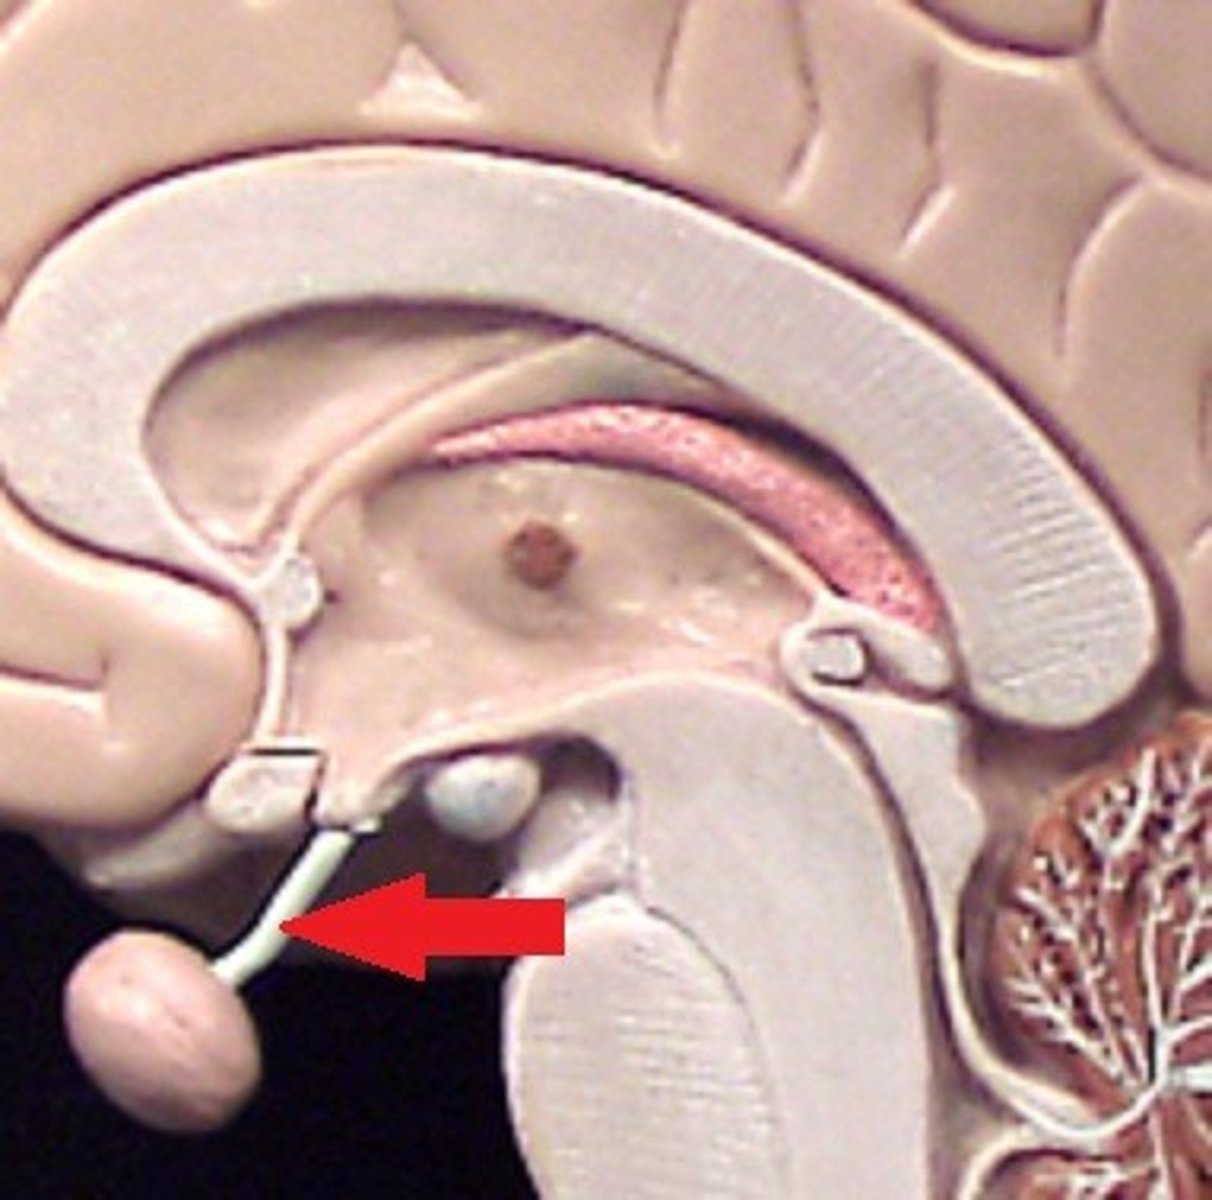

branches of olfactory nerve (cranial nerve I)

double check this

olfactory bulbs

olfactory tracts

double check this